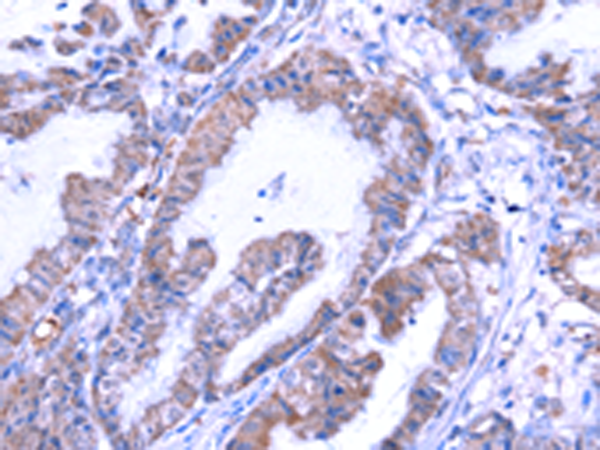

分类: 科研抗体货号: P01895别名: TBG; TBGQTL应用: WB,IHC反应种属: Human, Mouse